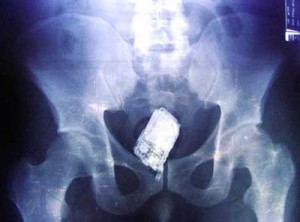

Agentes penitenciários do Conjunto Penal de Itabuna ficaram surpresos na hora de uma revista de rotina na manhã desta sexta-feira (30), em que um detento portava uma arma e um celular. Utilizando um detector de metais foi identifida a presença de objetos na região das nádegas do interno. O homem tinha uma pistola 635, calibre 22 e um celular inseridos no ânus.

Foto: divulgação / Blog do Tom